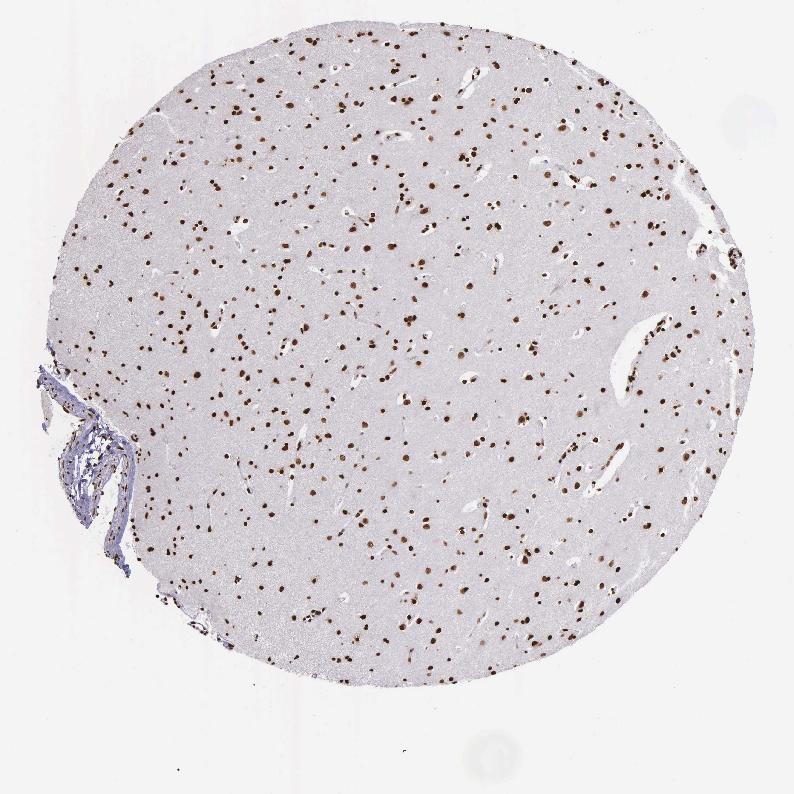

CAUDATE - Antibody stainingi

Antibody staining in the annotated cell types in the current human tissue is reported as not detected, low, medium, or high, based on conventional immunohistochemistry profiling in selected tissues. This score is based on the combination of the staining intensity and fraction of stained cells.

Each image is clickable and will lead to virtual microscopy that enables deeper exploration of all samples and also displays staining intensity scores, fraction scores and subcellular localization as well as patient and tissue information for each sample.

Antibody HPA000843

Glial cells High

Neuronal cells High